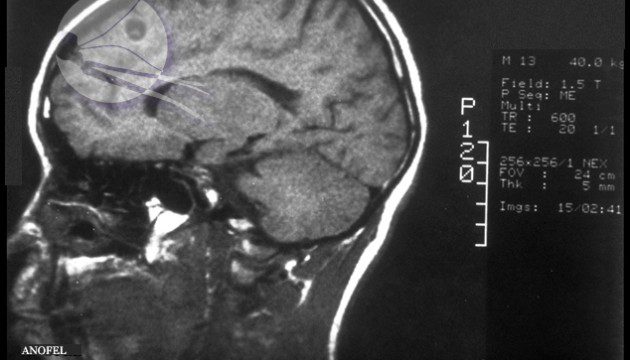

Ver Solitaire : Étudiant Victime d’un Parasite Cérébral

Résumé : Ver Solitaire Un étudiant américain présentait des migraines sévères, diagnostiquées plus tard comme [...]